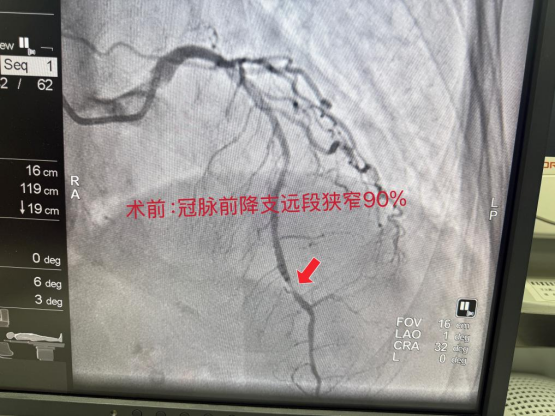

冠脉造影显示,老人冠状动脉前降支远段严重狭窄,心肌供血濒临中断,随时可能危及生命。

医疗团队身着沉重铅衣,沉着应战、精准操作,凭借多年临床经验与娴熟技术,精准定位病变血管,顺利实施药物球囊治疗,成功开通闭塞血管,让缺血心肌重新恢复血流灌注。